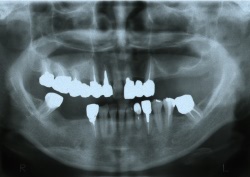

●黒く写っているのが上顎洞です。

このままでは、上顎洞までの距離が短く、インプラントができません。

●人工骨を填入して骨を作ります。

●骨ができたら、インプラントの処置を行います。